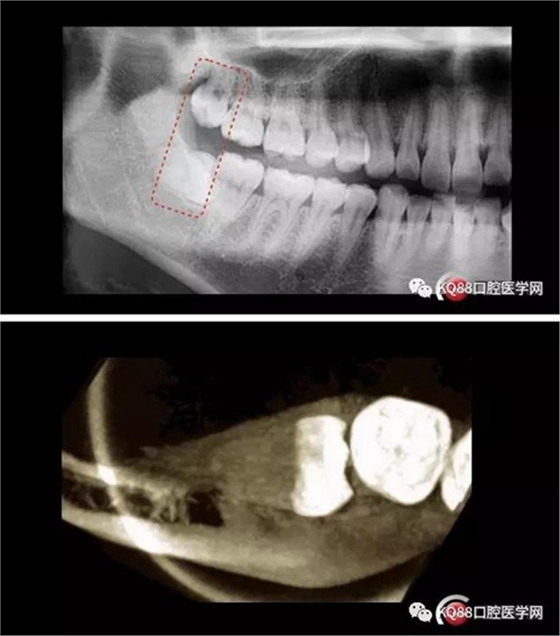

智齒拔除

來源:KQ88口腔醫(yī)學(xué)網(wǎng)